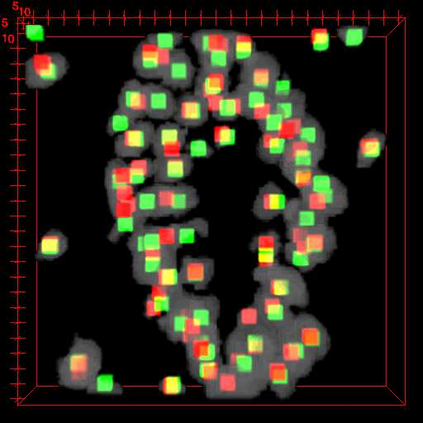

Robust and accurate nuclei centroid detection is important for the understanding of biological structures in fluorescence microscopy images. Existing automated nuclei localization methods face three main challenges: (1) Most of object detection methods work only on 2D images and are difficult to extend to 3D volumes; (2) Segmentation-based models can be used on 3D volumes but it is computational expensive for large microscopy volumes and they have difficulty distinguishing different instances of objects; (3) Hand annotated ground truth is limited for 3D microscopy volumes. To address these issues, we present a scalable approach for nuclei centroid detection of 3D microscopy volumes. We describe the RCNN-SliceNet to detect 2D nuclei centroids for each slice of the volume from different directions and 3D agglomerative hierarchical clustering (AHC) is used to estimate the 3D centroids of nuclei in a volume. The model was trained with the synthetic microscopy data generated using Spatially Constrained Cycle-Consistent Adversarial Networks (SpCycleGAN) and tested on different types of real 3D microscopy data. Extensive experimental results demonstrate that our proposed method can accurately count and detect the nuclei centroids in a 3D microscopy volume.